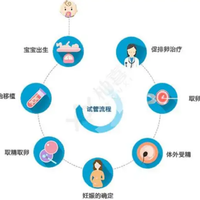

泰国试管婴儿 泰国三代试管价格一览表 1天前·22人浏览 泰国三代试管助孕正规机构费用大概多少?至于众多家庭来说,生育1个健康宝宝是最大的夙愿。然而,由于各类缘由,一些家庭可能需要借助人类辅助生殖技术,例如试管婴儿(试管婴儿(IVF))。泰国作为医疗旅游的热点目的地,其试管婴儿技术也备受注意,尤其是第三代试管婴儿(PGD/PGS)技术。